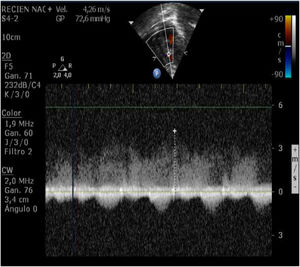

We performed an enzimatic curve, an ultrasound image and an ultrasound continuous doppler (Fig. 2) and there were not any evidence of myocardial ischemia. The patient remained asypmtomatic during the hospital stay and progressed correctly. Spontaneous closure of the CAF occurred one month after the initial diagnosis.